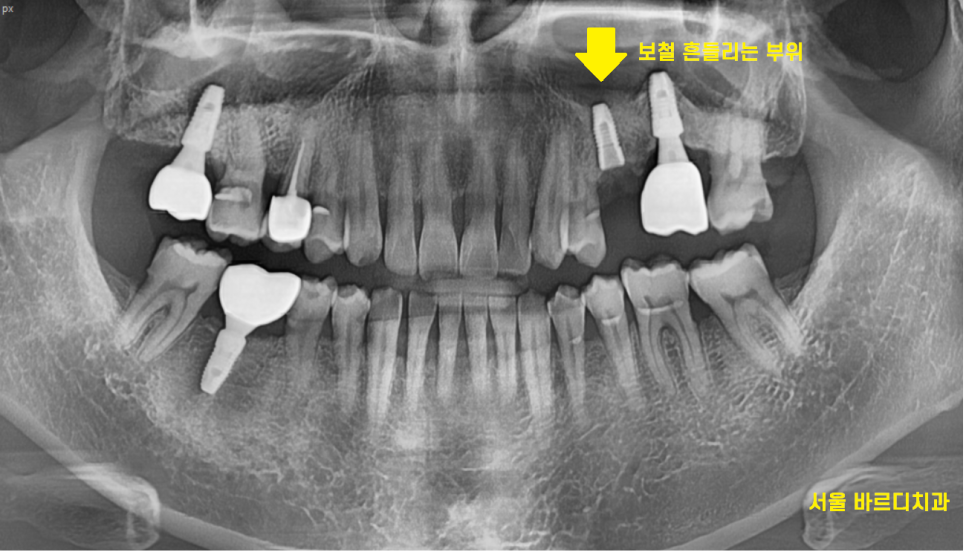

임플란트 보철 흔들림으로 길동 치과를 내원하신 환자분입니다.

임플란트 보철 흔들림 원인이 되는 치아를 제거해보았는데요

원인을 파악하기 위하여 찍은 ct에서

임플란트가 찢어진 모습을 관찰하였습니다.

이럴 경우 아무리 나사를 조여들여도

계속해서 임플란트 보철 흔들림 발생할 수 밖에 없는데요.

수명이 다 한거죠ㅠㅠㅠ